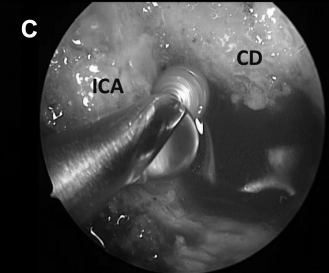

▼切开ICA颈内动脉下方的破裂孔处的韧带(图8D)。

▼从该切口可暴露右颈静脉结节区域的充足手术通道(图8E和F)。

CD,斜坡凹陷;S,蝶鞍;SR,蝶嘴;T,肿瘤。